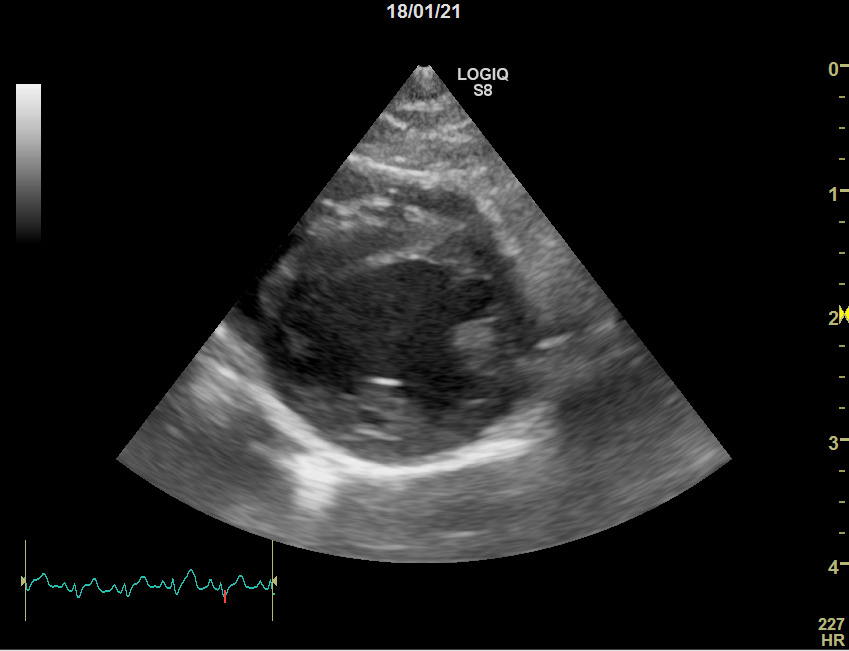

正常な犬

心臓病(僧帽弁閉鎖不全症)の犬

僧帽弁閉鎖不全症の犬では僧帽弁が厚くなり、きちんと弁がしまっていません。